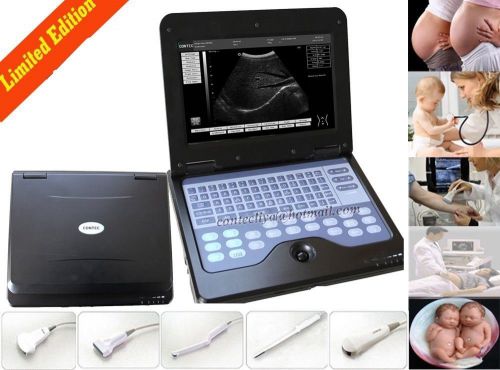

Model | RUS-9000E2 |

Portable Hot Ultrasound Diagnostic Scanner machine+3.5MHz Convex Probe,Sales

On Sale!!Portable Hot Ultrasound Diagnostic Scanner machine+3.5MHz Convex Probe

Promotion CMS600P2 New Portable laptop ultrasound scanner 3.5 Convex,2y warranty

3D PC Full-digital Ultrasound scanner machine 3.5MHz Convex + Linear+ Tvaginal

3D PC Full-digital Ultrasound scanner machine 3.5MHz Convex +mirco-Convex probe

3D Full Digital Laptop Ultrasound Scanner (PC) With Convex probe & Transvaginal